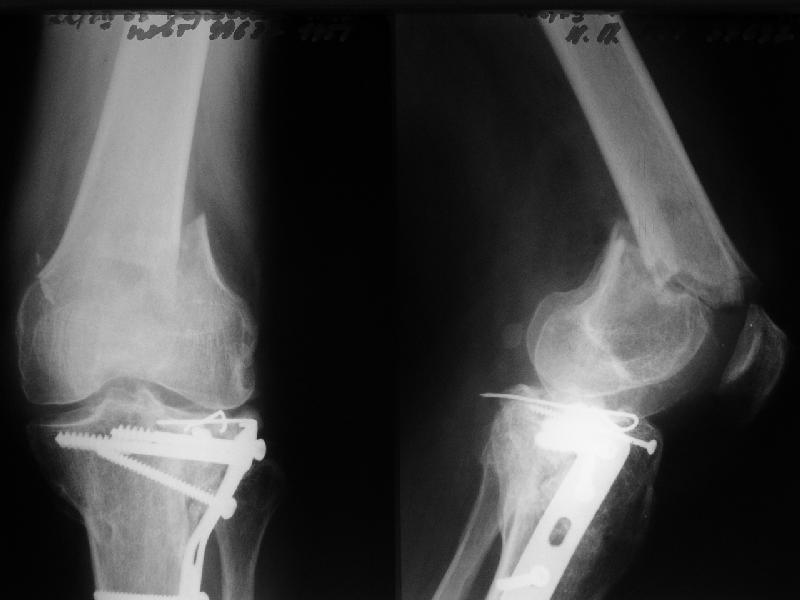

1

In the supracondylar nail system both the ends are lockable by jig and no free hand technique is needed.

I do not see the proximal bolts; I presume they must be at he trochanter level. In a supracondylar nail you are able to see both side bolts in one picture. ( Enclosure)